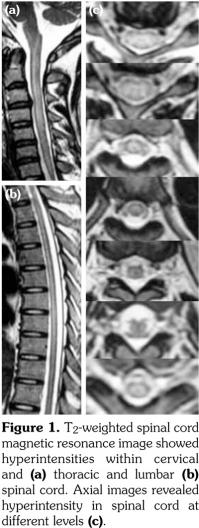

A 22-year-old male patient was admitted with one-week of headache, vomiting, and urinary incontinence. Before admission, he had felt motor weakness for two years and noticed recurrent genital and oral ulcers with a frequency of more than three episodes per year for five years. He had no visual impairment. There were no cutaneous lesions such as papules, macules, ecchymosis or nodules. The pathergy test was positive. On neurological examination, he had impaired muscle strength in the upper (phase-4 on both sides) and lower (phase-4 in the left and phase-3 in the right) extremities. His impairment level according to American Spinal Injury Association classification was D. He was able to walk only by assistance from his parents or a walking stick. Pathological reflexes such as the Hoffmann and Babinski signs were present bilaterally. Abdominal reflex, cremasteric reflex, tendon reflexes disappeared bilaterally. He had a sensory level at C2 on the right and T2 on the left. Routine biochemical tests showed an increased erythrocyte sedimentation rate (85 mm/h) and C-reactive protein level (124 mg/L). Serum autoantibody tests were negative for anti-nuclear antibody, anti-aquaporin-4 antibody, and other autoantibodies. His cerebrospinal fluid (CSF) contained 230 cells/uL (124 lymphocytes and 106 neutrophils) and 852.8 mg/L protein. Ink, gram and acid-fast staining of his CSF were negative. Cultures of his CSF yielded no bacterial growth. Cranial magnetic resonance imaging and magnetic resonance angiography and venography showed no abnormalities. T2-weighted spinal magnetic resonance images (Figure 1) showed hyperintensities within the entire spinal cord. He was diagnosed with longitudinal myelitis associated with NBD.